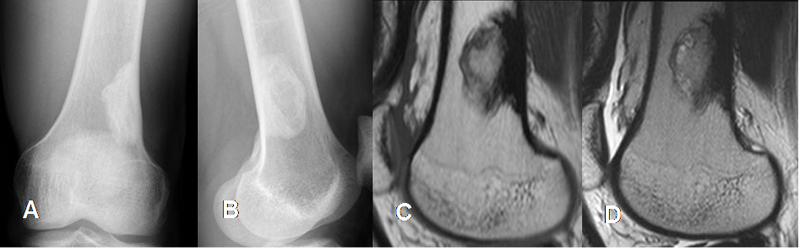

Fig 97 A. Defecto fibroso cortical.

A: Rx AP y B: Rx Lateral. Imagen densa y de bordes bien definidos en el fémur distal.

C: RM sagital en T1 y D: RM sagital en T2. La imagen es hipointensa en ambas secuencias, por su alto contenido fibroso y de bordes escleróticos, correspondiendo a lesión residual de un defecto fibroso cortical.